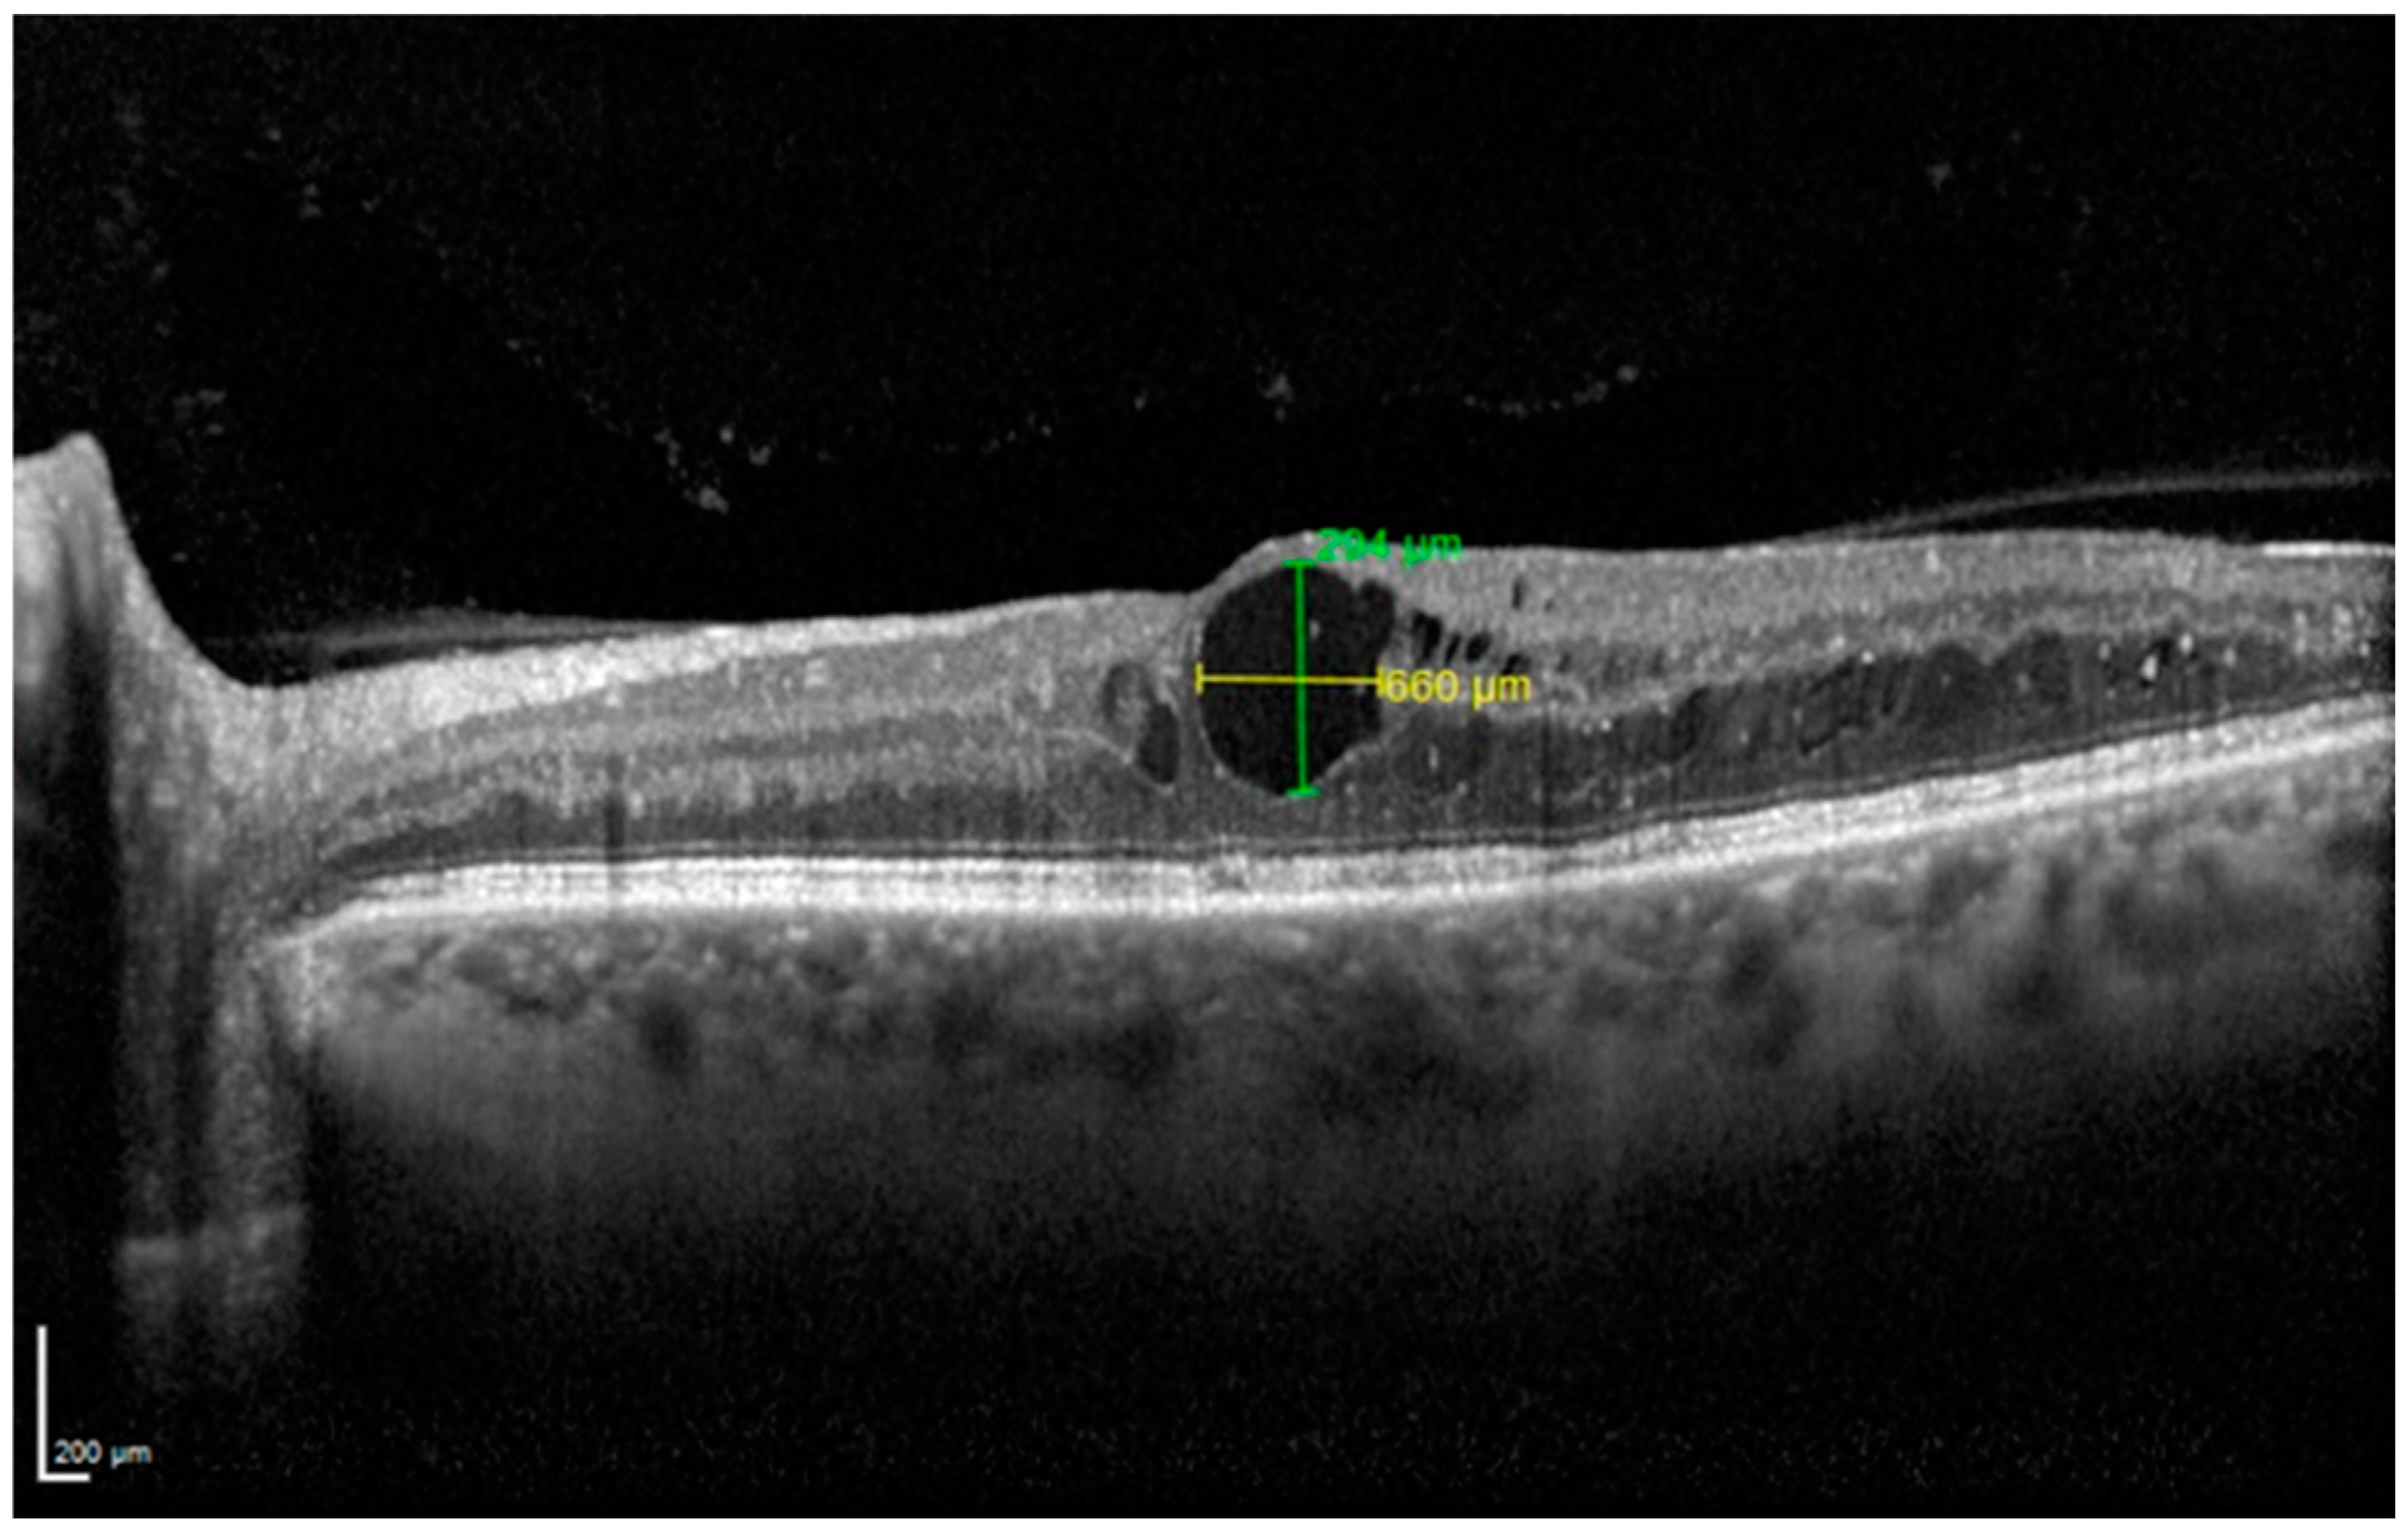

| Central Subfield Thickness, µm (mean ± SD) | 496.93 ± 79.06 | 379.93 ± 116.96 | 0.0001 | 353.53 ± 116.11 | 0.0081 | 334.73 ± 111.99 | 0.0017 | 318.47 ± 99.58 | 0.0073 | 300.67 ± 84.61 | 0.0017 |